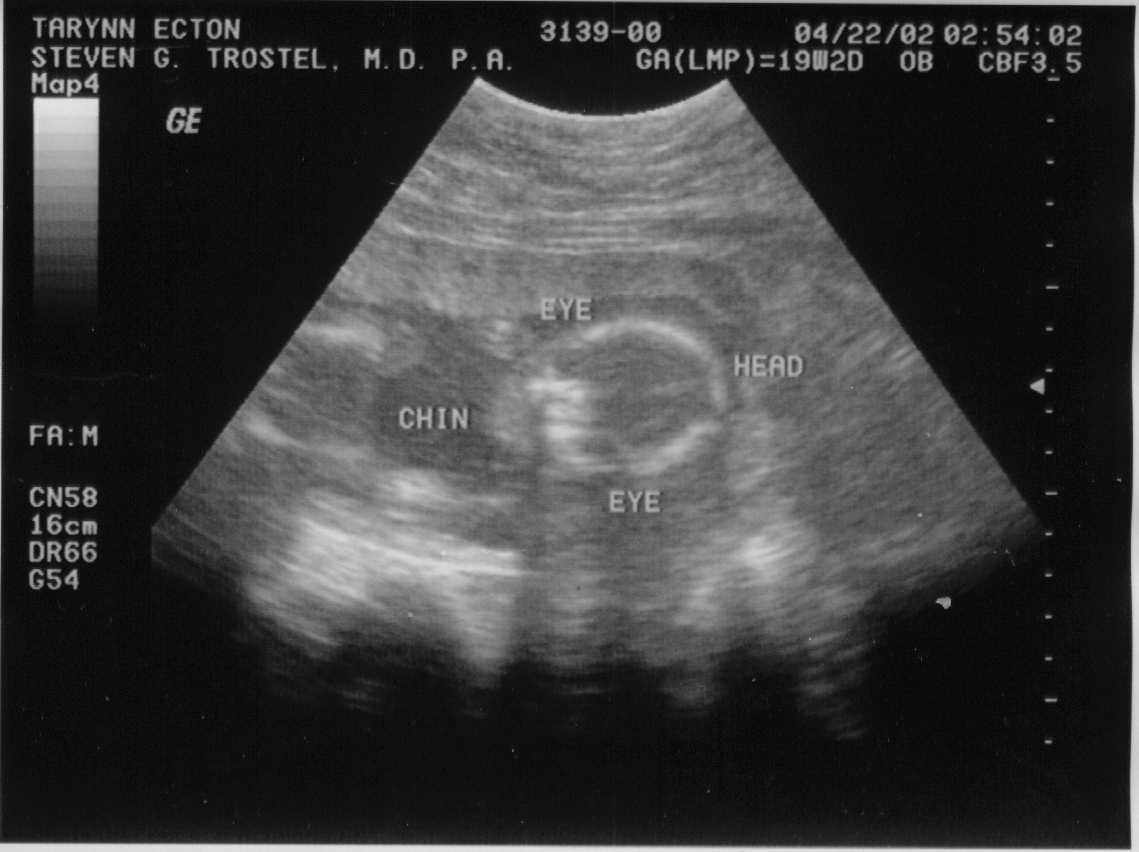

Second Sonogram, taken 04-22-02.